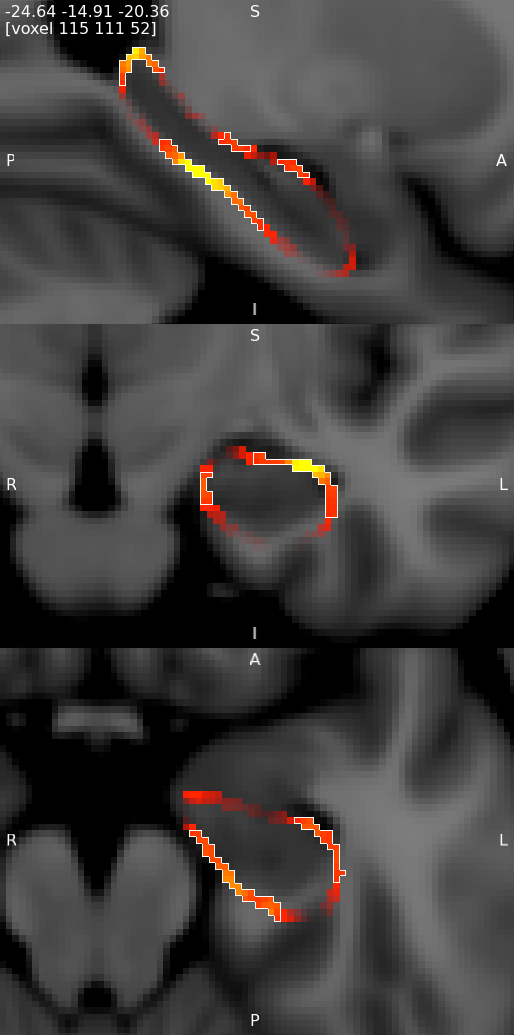

Output of vertex analysis

In the same way as in FSL-VBM and TBSS, randomise is used to generate the statistics. The output of most interest is the probability that is corrected for multiple comparisons. This will contain corrp in the filename. The values within this file contain 1-p values, such that p=0.05 corresponds to a value of 0.95, and so displaying all values over 0.95 with FSLeyes will show the significant areas. For more information about how to view these results refer to the documentation for randomise, FSL-VBM or TBSS.

Results from randomise can be viewed in the standard orthographic or lightbox views in FSLeyes. To distinguish the direction of the changes see the description in the section on randomise above.

Viewing results in 2D

A useful option when displaying statistical results is to view the statistic image (e.g. the f-statistic, t-statistic image, etc), and to highlight significant regions with the corrected P-value image. This can be accomplished in FSLeyes like so:

- Start up FSLeyes, and add the following as overlays, ensuring that they are ordered in this way in the overlay list:

- the corrected P value image, e.g.

con1_dis2_L_Hipp_rand_clustere_corrp_fstat1.nii.gz - the statistic image that you want to visualise, e.g.

con1_dis2_L_Hipp_rand_fstat1.nii.gzto display the F-statistics from therandomisecall above. - The MNI152 1mm standard template

- Open the overlay display dialog (the gear button at top-left).

- Select the P-value image in the overlay list, and in the overlay display dialog change these settings:

- Overlay data type to 3D/4D mask image

- Show outline only selected

- Select the statistic image in the overlay list, and in the overlay display dialog adjust the display settings as desired - for example, you can set up a red/blue positive/negative colour display suitable for many statistic values with the following settings:

- -ve colour map selected

- First colour map set to Red-Yellow

- Second colour map set to Blue-Light blue

- Modulate alpha by intensity selected - this causes regions with a low value to be made transparent

- Display range and Modulate range adjusted as desired